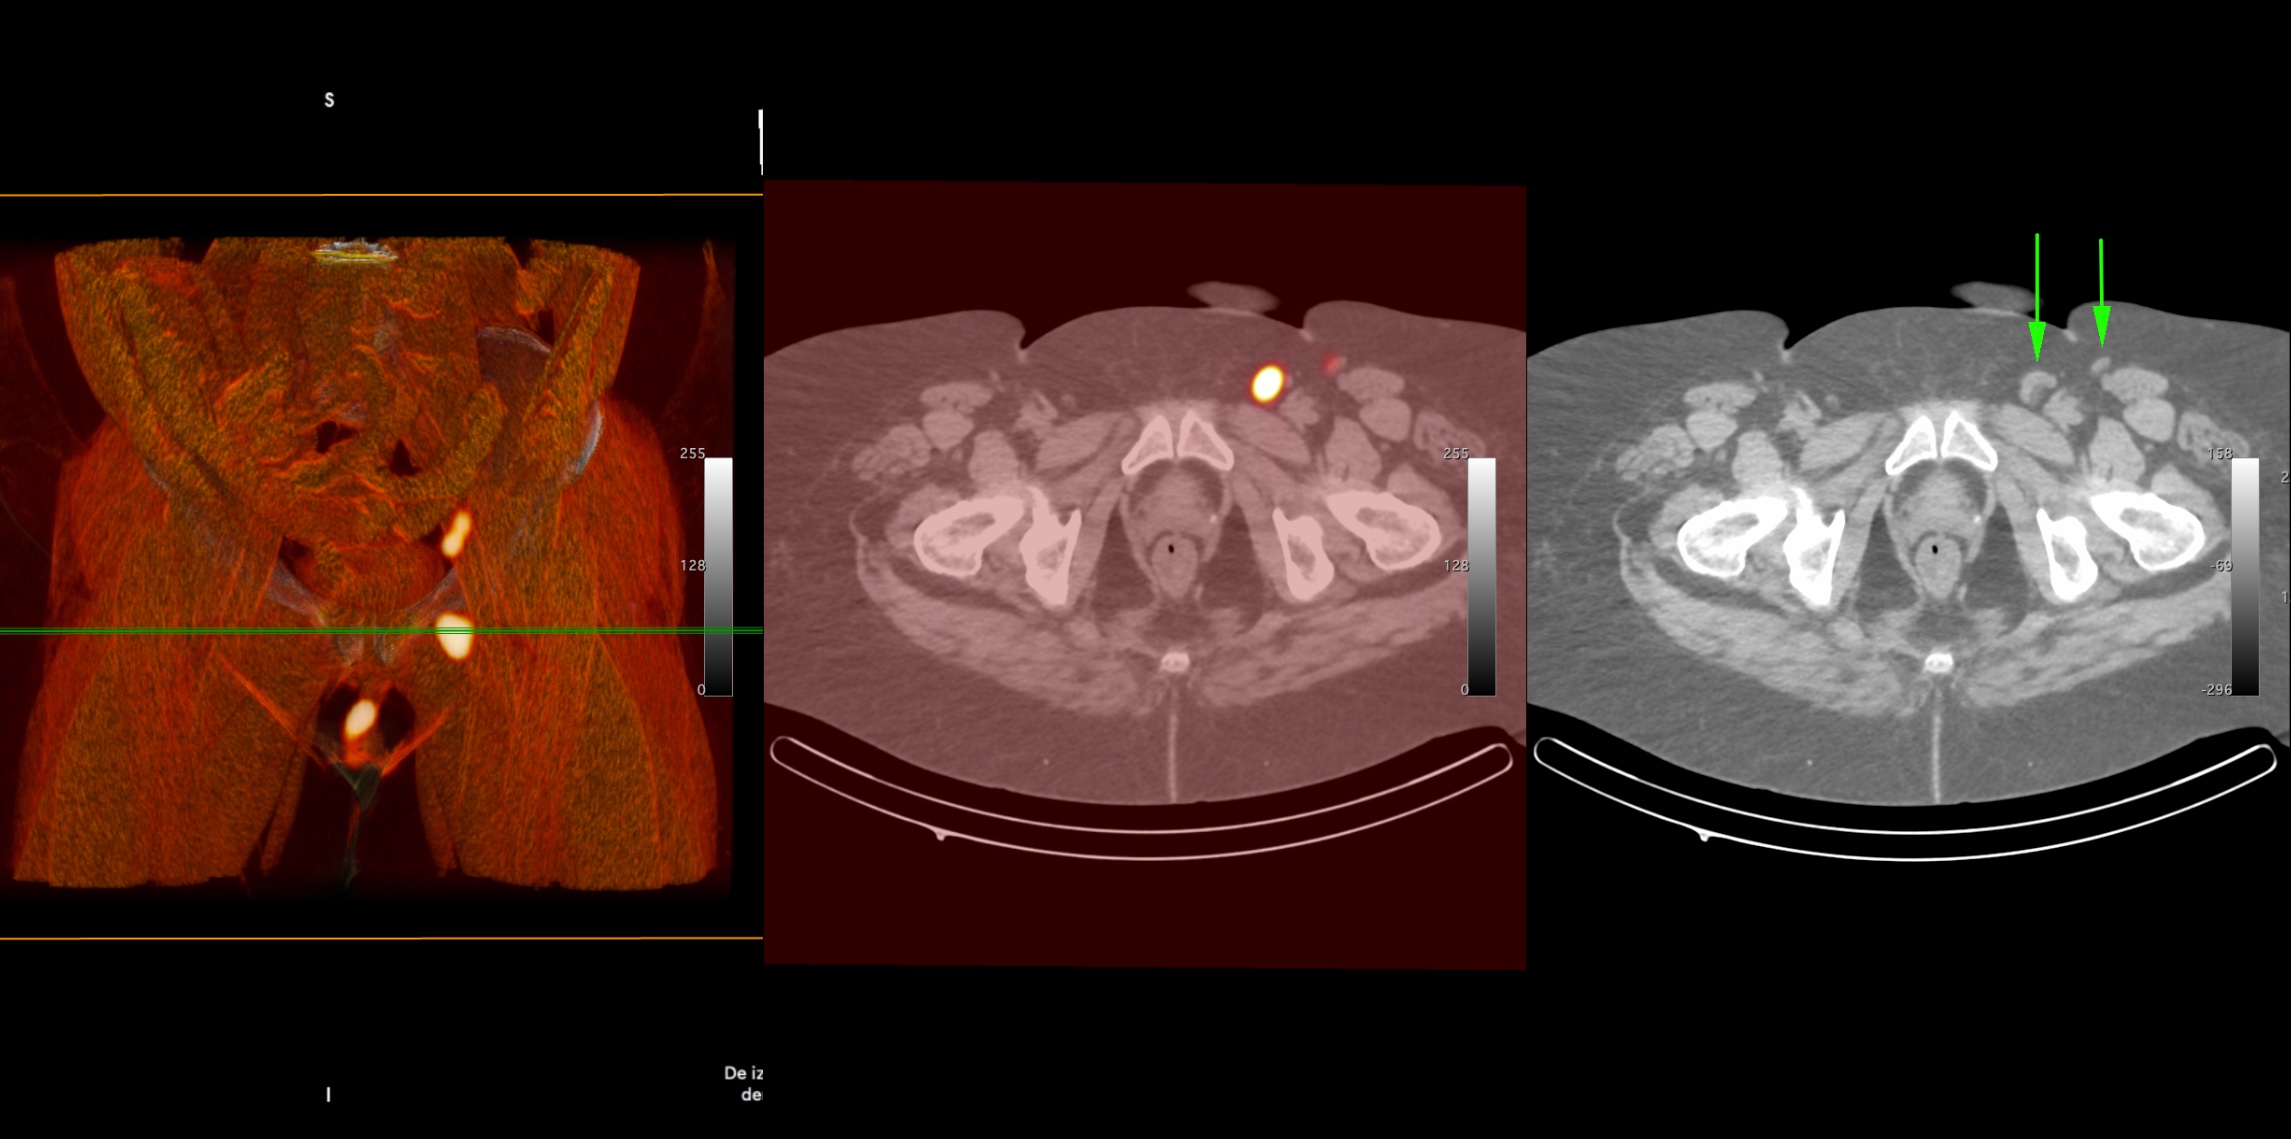

Imaging of a patient with vulvar cancer showing two sentinel lymph nodes in the left inguinal region (green arrows), the injection site, and secondary lymph nodes in the left iliac region. (Photo: S. Vidal)